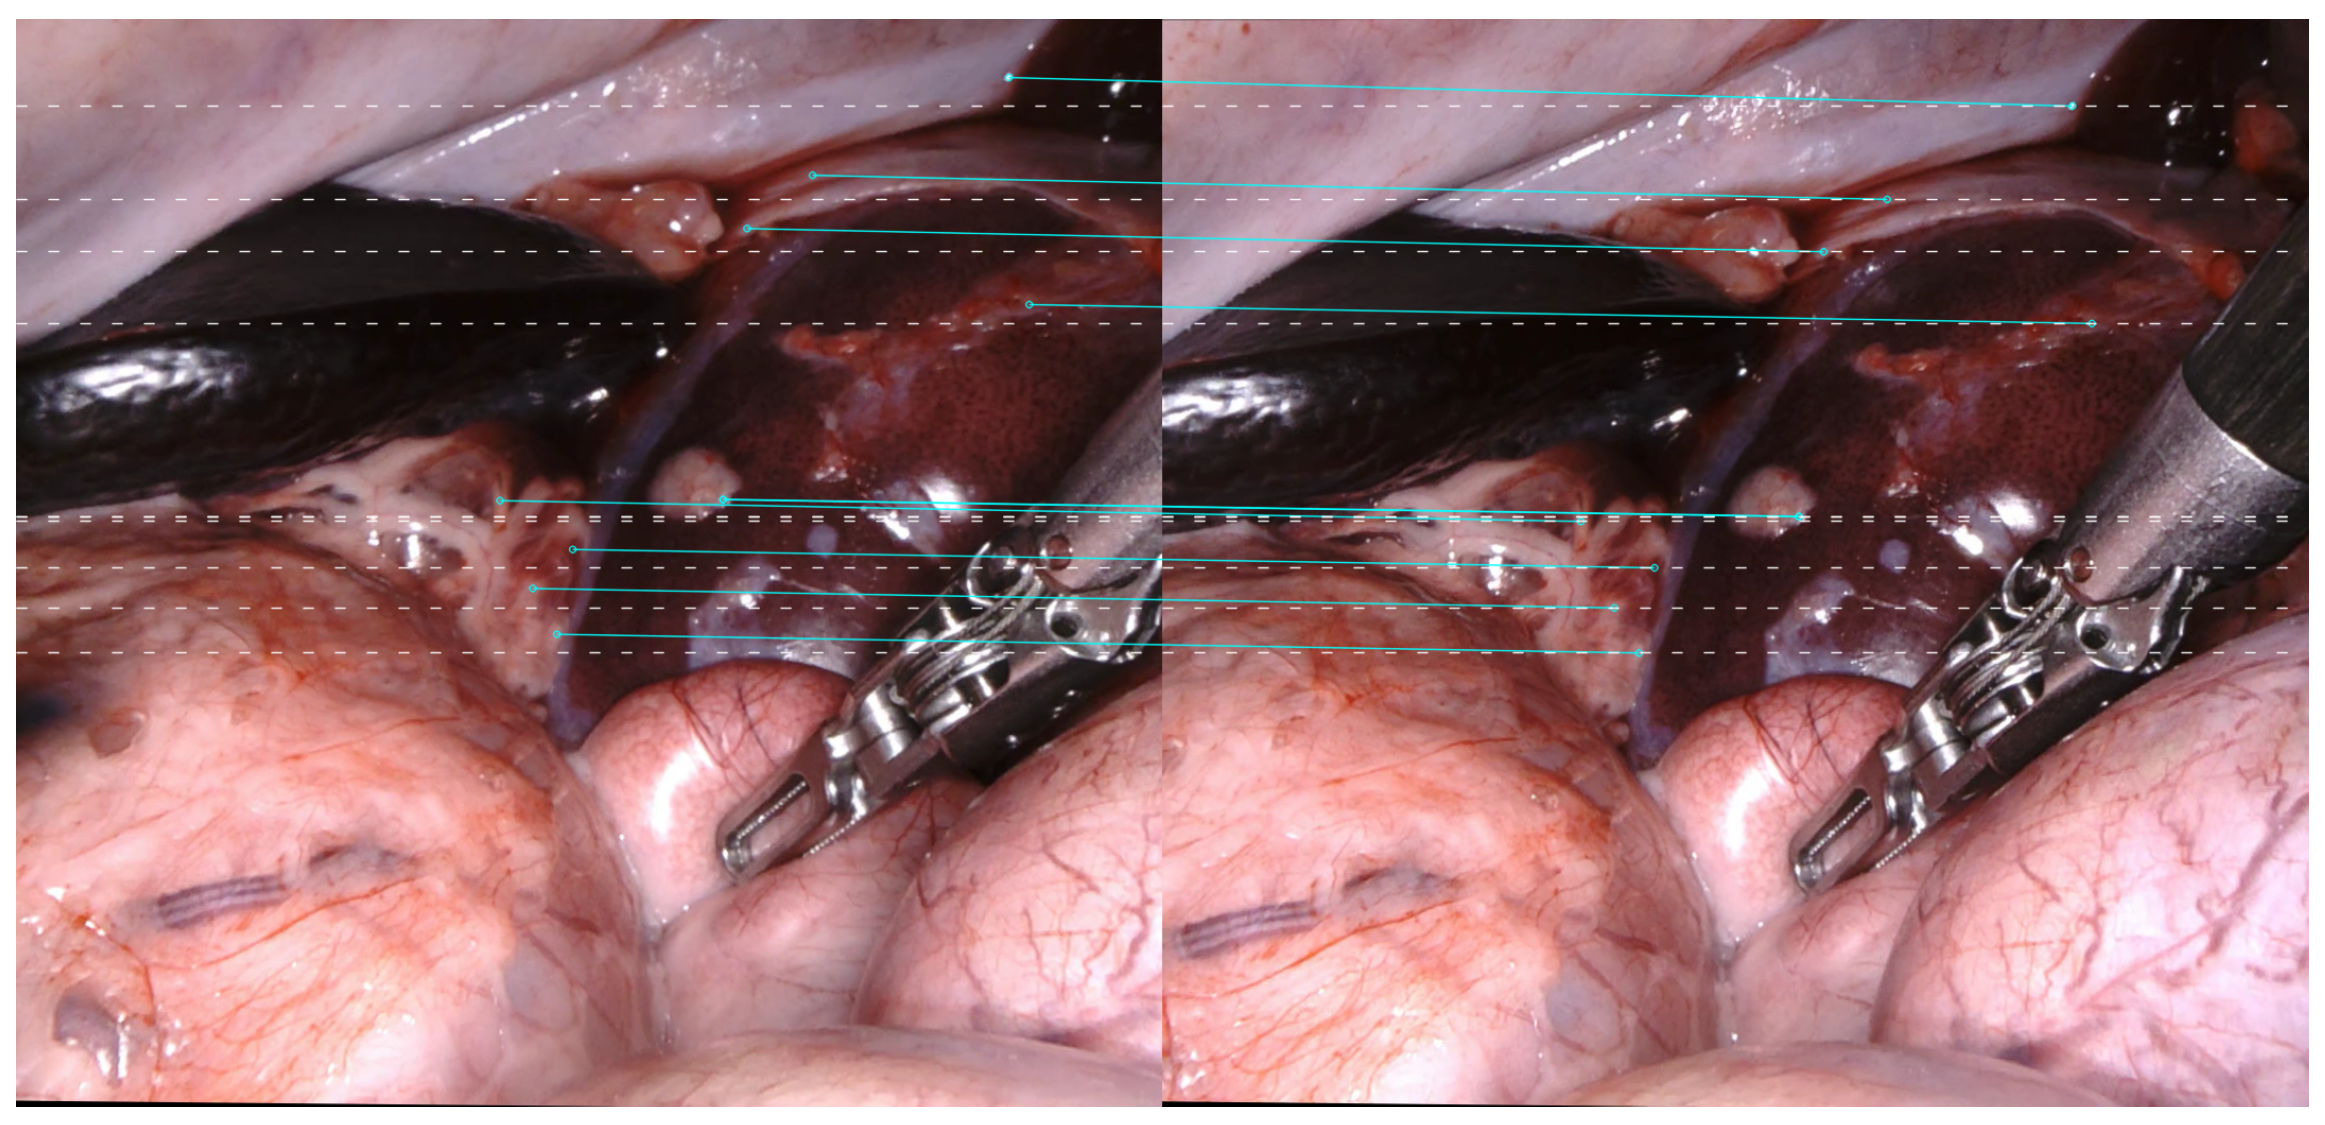

2.2. Stereo Matching for Laparoscopic Images

4.1. Datasets and Metrics